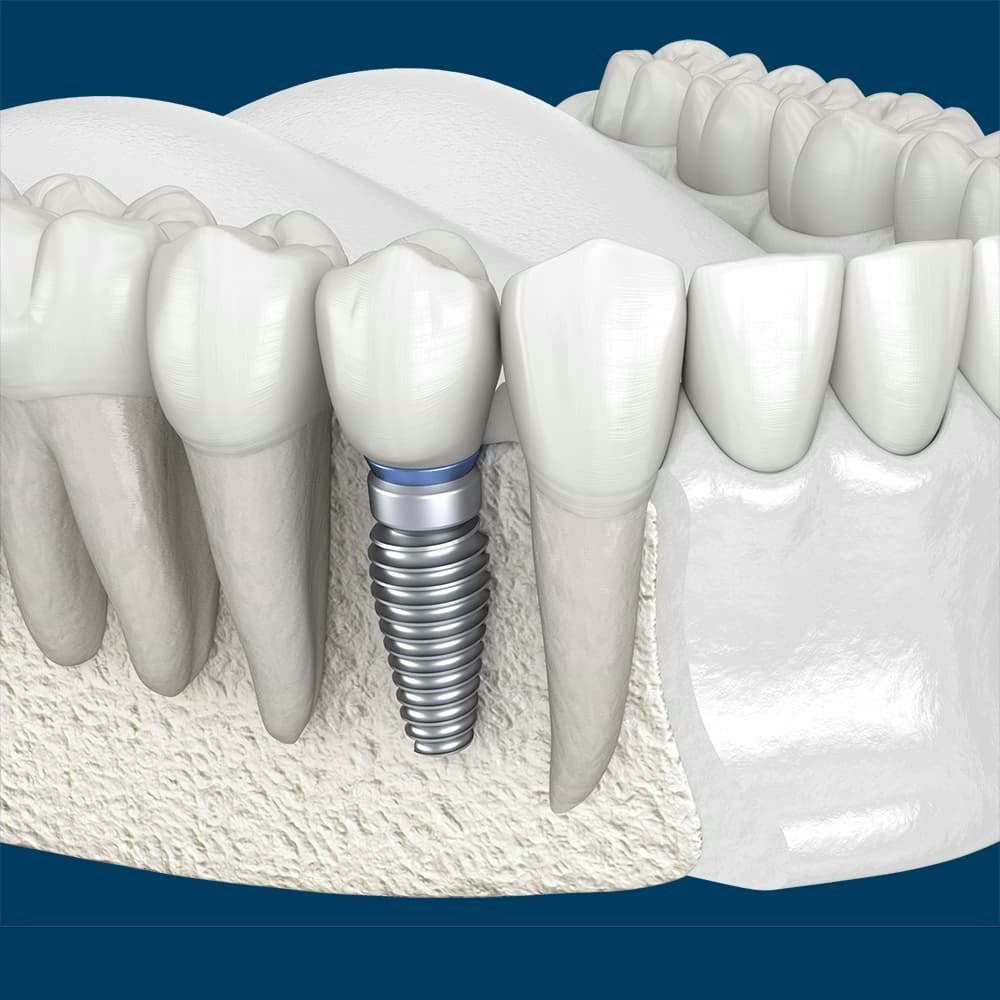

- Dental implants

Dental Implants

The ultimate goal for a maxillofacial surgeon is to repair any damage done and restore function to your smile. What those results will look like depends on the patient's needs and the treatments in question. While frenectomy or extraction will have immediate results, placing dental implants or completing corrective jaw surgery requires months of recovery before your body adjusts.